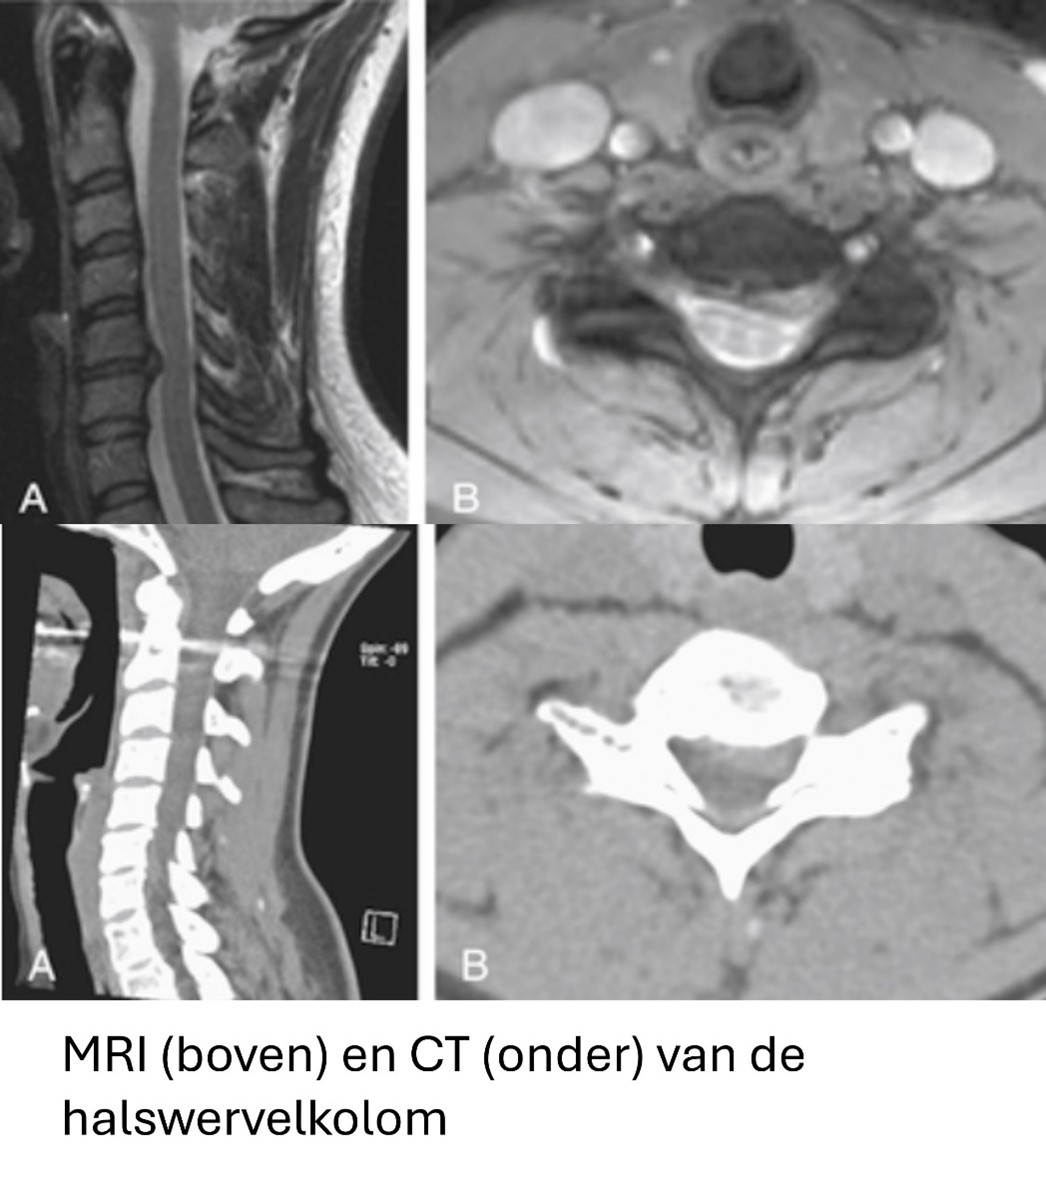

Beeldvormende onderzoeken: MRI-scan

Aanvullend op het klinisch onderzoek worden beeldvormende onderzoeken uitgevoerd, zoals een MRI-scan of een CT-scan van de cervicale wervelkolom. Deze scans bieden gedetailleerde beelden van de wervelkolom en kunnen de aanwezigheid, locatie en omvang van de hernia nauwkeurig vaststellen. Een MRI is vaak de voorkeursmethode omdat het gedetailleerde informatie geeft over de zachte weefsels, inclusief de zenuwwortels die mogelijk bekneld zijn. Een MRI-scan maakt gebruik van magnetische velden en geeft dus geen stralenbelasting voor het lichaam. Het is wel van belang om het tijdens het gesprek met uw arts aan te geven als u metalen implantaten, een pacemaker of andere elektrische implantaten heeft.

Beeldvormende onderzoeken: CT-scan

Bij een CT-scan worden er Röntgenstralen gebruikt. Het is van belang om de blootstelling aan Röntgenstralen te beperken. Daarom zal het gebruik van een CT-scan worden beperkt tot specifieke gevallen, bijvoorbeeld als er een gedetailleerd beeld van het skelet moet worden verkregen of als door implantaten een MRI niet goed mogelijk is.